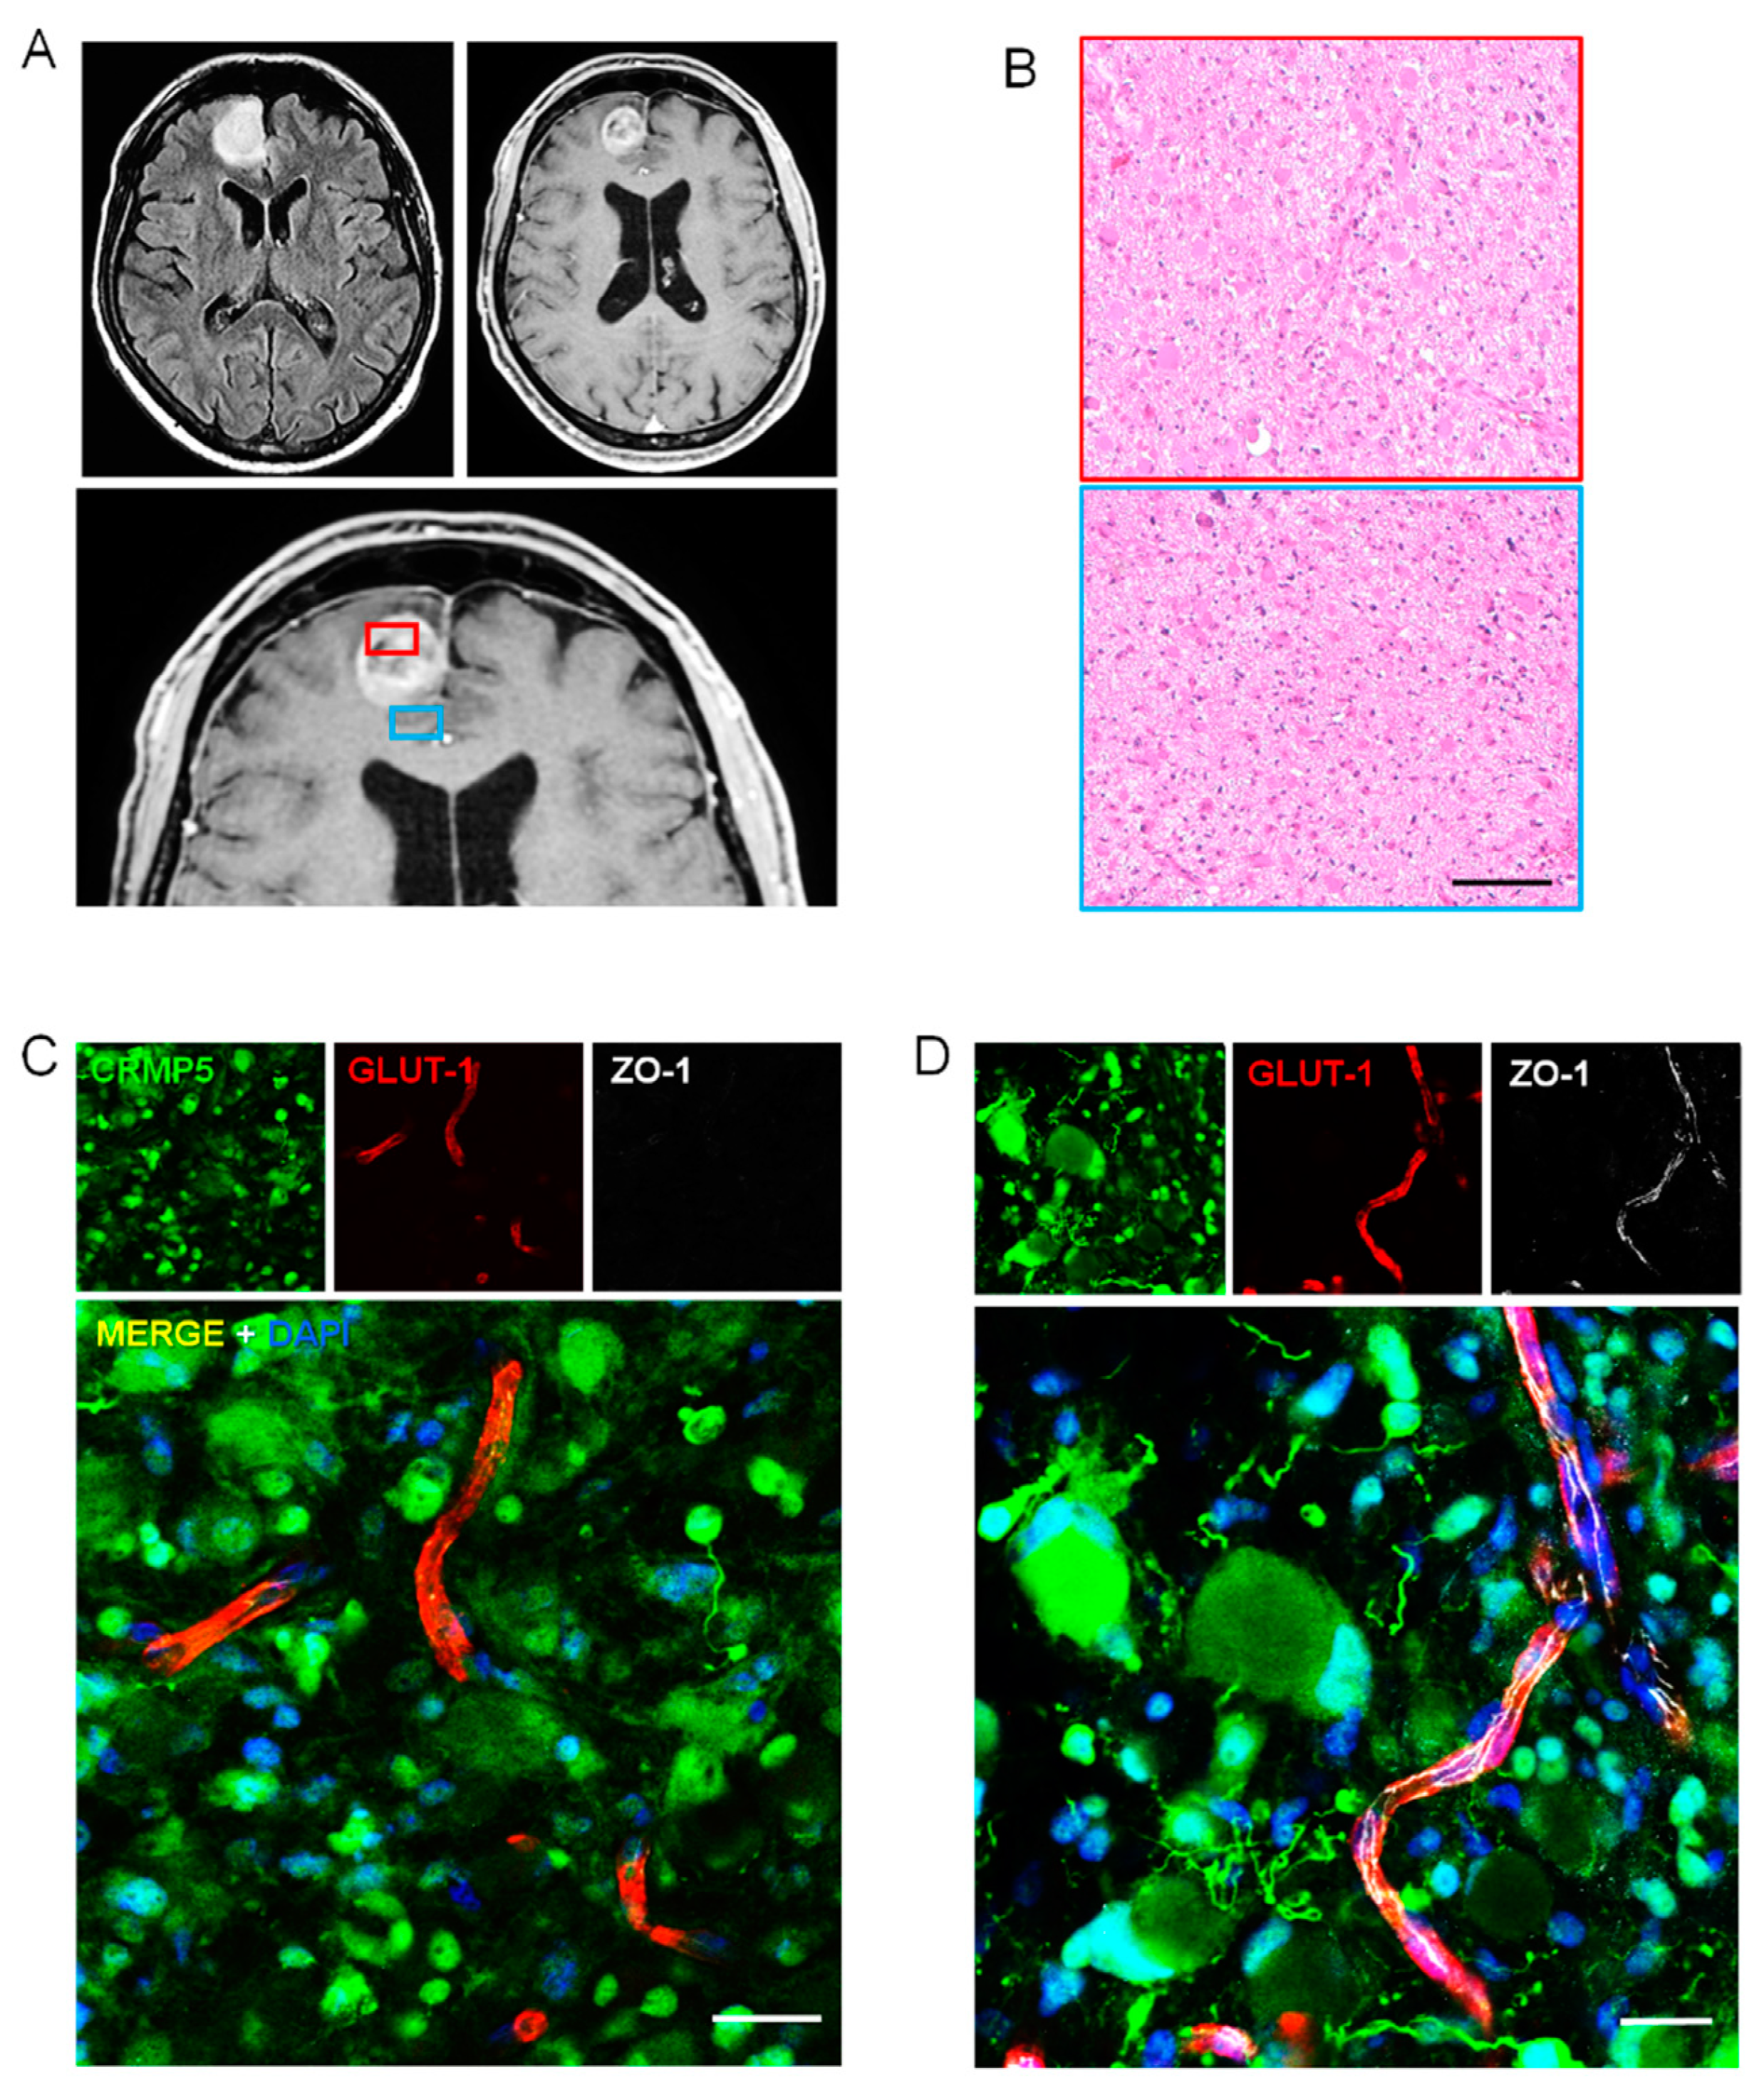

2.2. Perivascular Invasion and Disruption of BBB in Human Specimens of Gliomas